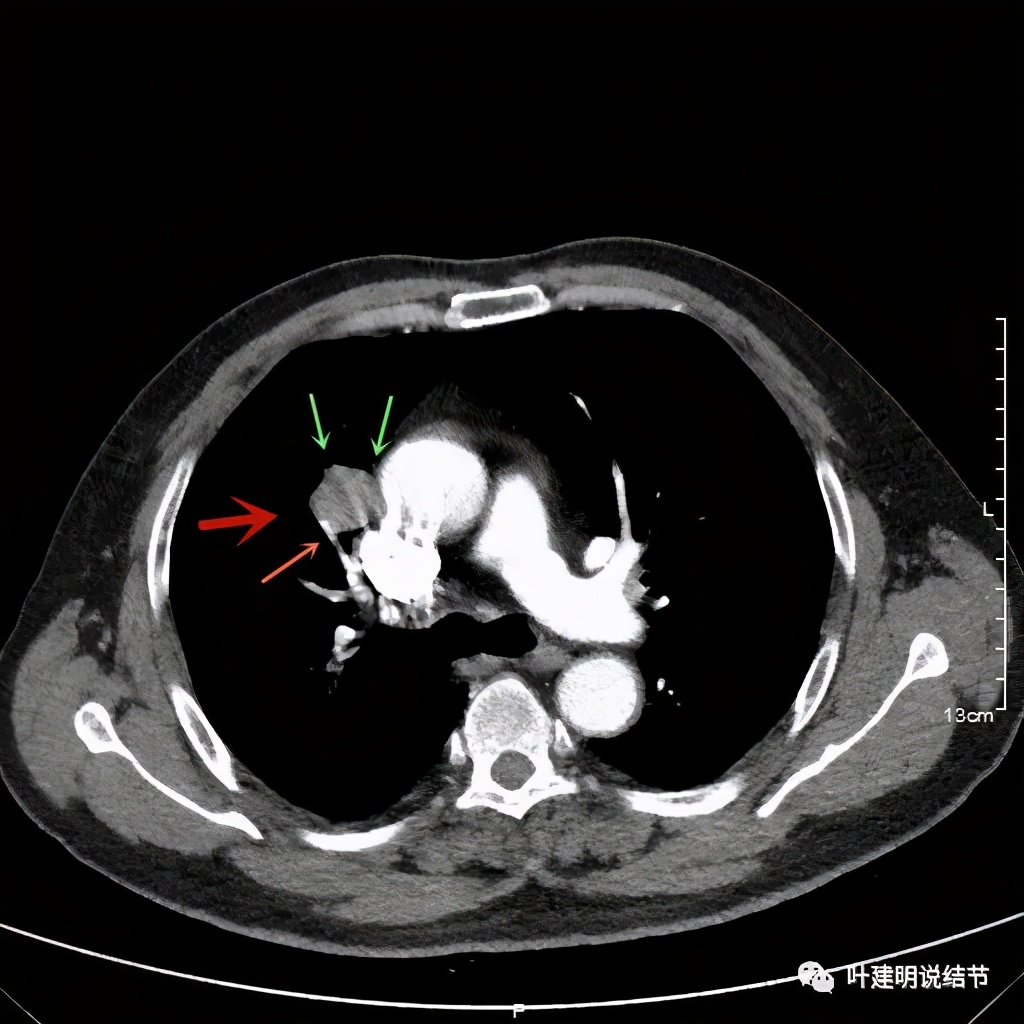

上图示病灶密度不均

上图示病灶密度不均,但边缘过于光滑(绿色);支气管似有截断(粉色);局部有点状钙化(蓝色)

上图也示病灶密度不均,但边缘过于光滑(绿色);支气管似有截断(粉色);局部有点状钙化(蓝色)